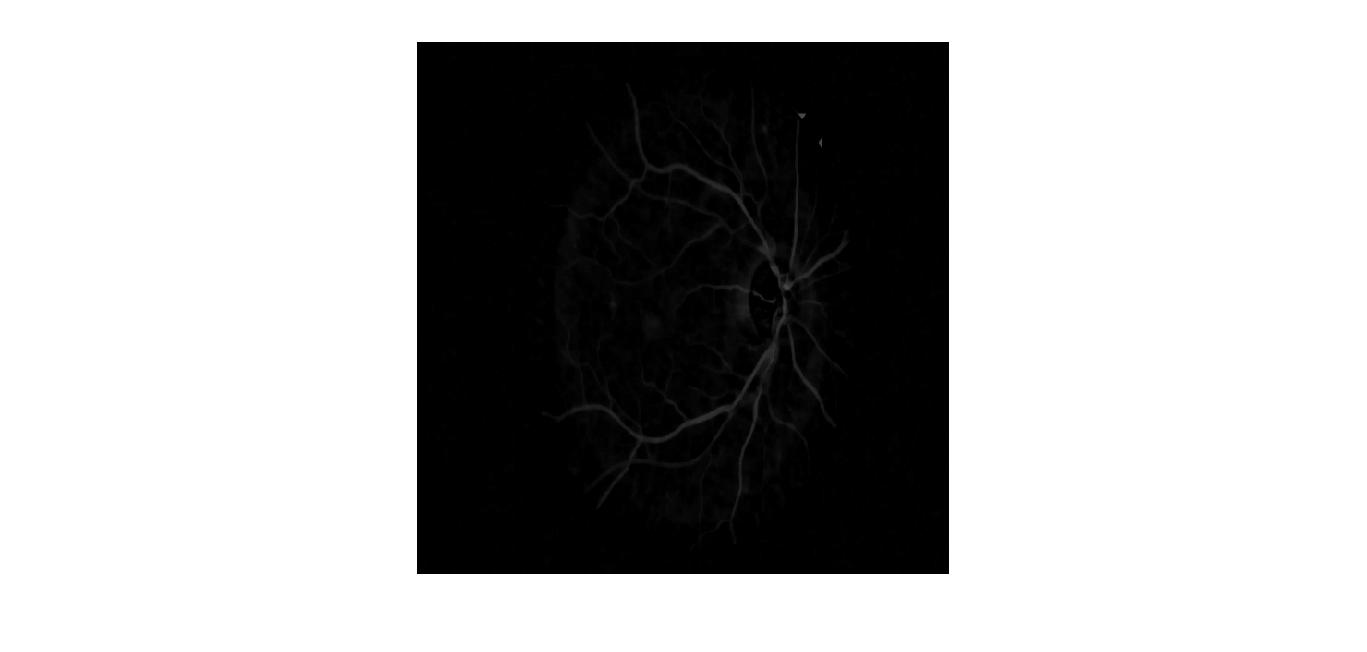

How to make the vessels brighter in this segmented image

I want to increase the pixels intensity of segmented blood vessels for a image like this